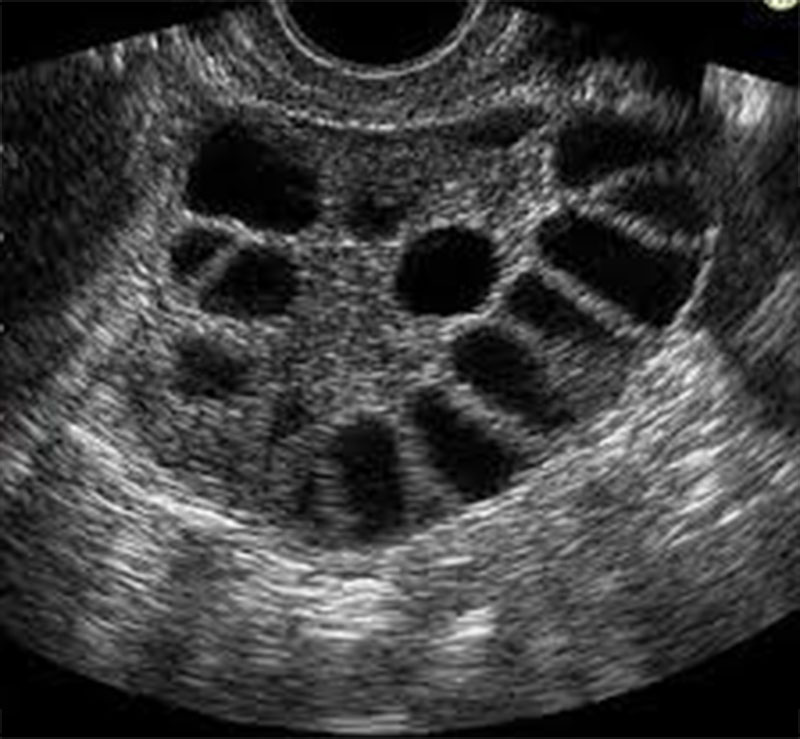

Με τον όρο πολυκυστικές ωοθήκες περιγράφουμε εκείνες τις ωοθήκες που περιέχουν πολλές μικρές κύστεις, οι οποίες συνήθως δεν ξεπερνούν τα 8 χιλιοστά σε μέγεθος, και που εντοπίζονται τις πιο πολλές φορές ακριβώς κάτω από την επιφάνεια της ωοθήκης. Οι μικρές αυτές κύστεις είναι ωοθυλάκια που περιέχουν ωάρια, λόγω όμως ορμονικών διαταραχών, τα ωοθυλάκια αυτά δεν έχουν αναπτυχθεί πλήρως και παρουσιάζουν στασιμότητα στη πορεία εξέλιξης τους. Οι πολυκυστικές ωοθήκες είναι συχνές στις γυναίκες και απαντώνται περίπου στο 20 – 30% των γυναικών

Κατά το υπερηχογράφημα σύνηθες εύρημα είναι οι πολυάριθμες μικρές κύστες περιφερειακά στην ωοθήκη. Επίσης βρίσκουμε συνήθως ένα παχύ ενδομήτριο (εσωτερική επένδυση της μήτρας) λόγω της άστατης εμμηνορρυσίας.